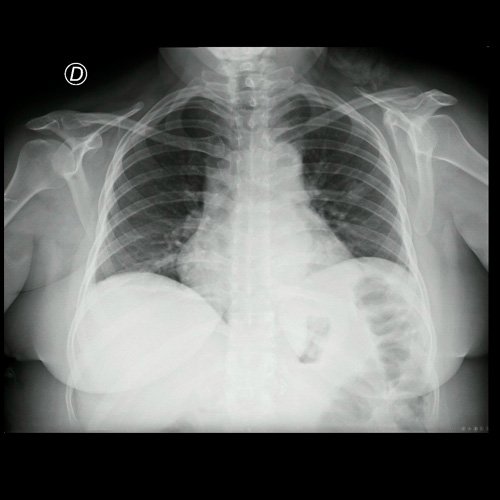

Radiografia de torax (frente) (al ingreso, 26/02/2026)

• Radiografía de tórax frente (DIA 1): centrada, índice cardiotorácico aumentado de tamaño, senos costofrénicos libres.